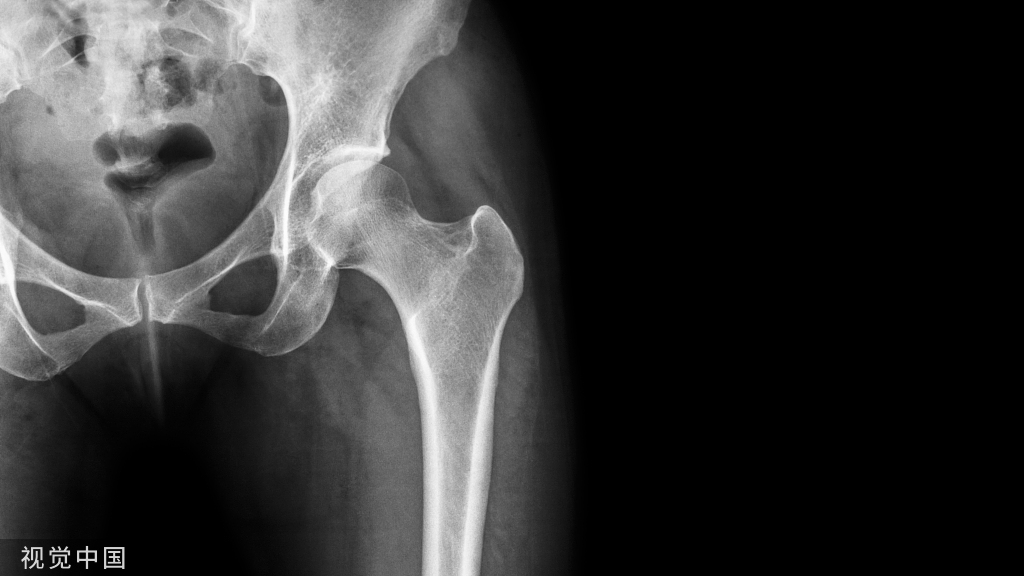

小儿骨科X线片汇总,临床读片宝典!